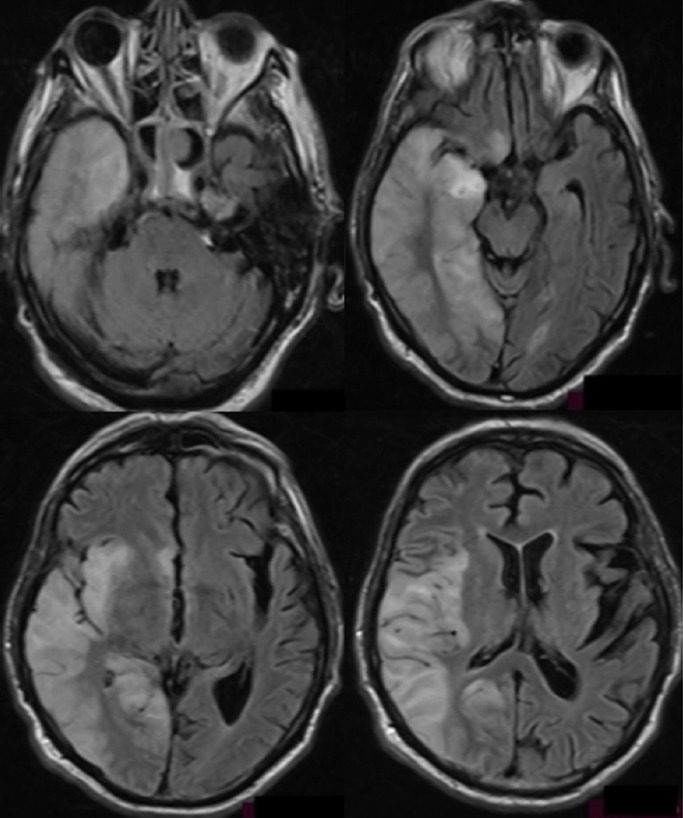

Herpes simplex encephalitis (HSE) is a potentially fatal infection of the brain parenchyma with high mortality rates when left untreated. It typically affects the medial temporal lobe, and patients commonly present with headache, fever, and altered mental status. The combination of clinical findings and brain imaging should raise suspicion, whereas cerebrospinal fluid (CSF) analysis should establish the diagnosis. In a few cases, HSE presents with subacute progression, making diagnosis more challenging. Treatment with acyclovir should begin immediately after HSE is suspected; otherwise, the mortality rate is high. Herein, we present a rare case of HSE with a subacute course admitted to the emergency department because of an episode of syncope with concomitant bradycardia. HSE symptoms developed gradually during the first week after hospitalization. Typical imaging findings, CSF analysis, and polymerase chain reaction results positive for herpes simplex virus-1 confirmed a diagnosis of HSE. The insidious symptomatology of this case led to delayed acyclovir administration and the patient unfortunately died 4 days after diagnosis.

Abstract Image